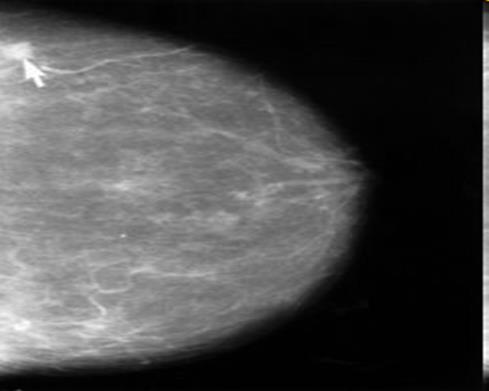

La mammografia è un esame del seno umano effettuato tramite una bassa dose (di solito circa 0.7 mSv) di raggi X.

Viene utilizzato come strumento diagnostico per identificare tumori e cisti.